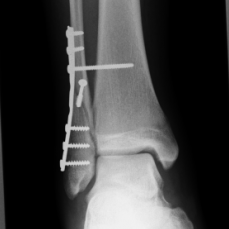

Röntgenbilder